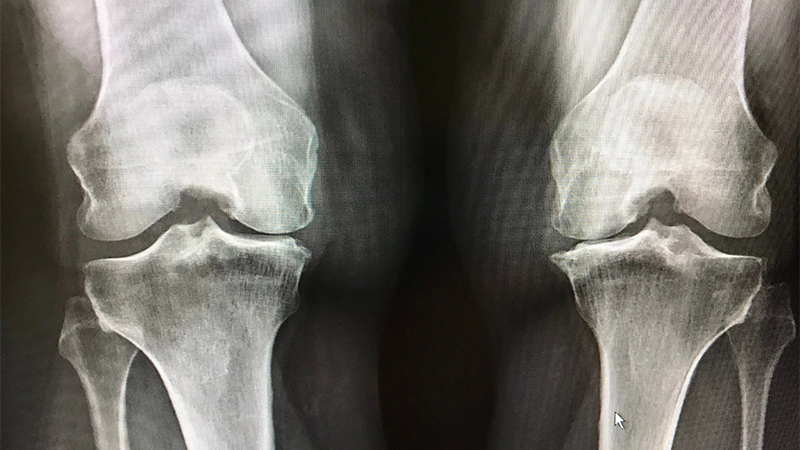

Diz Kireçlenmesi

En çok görülen eklem rahatsızlıklarından biridir. Diz eklemindeki kıkırdak aşınır, kemikler birbirine sürtünmeye başlar ve ağrı, sertlik ile hareket kısıtlılığı gibi belirtiler ortaya çıkar.

Bu durum genellikle yaşlanma süreciyle bağlantılı olmakla birlikte, spor yaralanmaları ve aşırı yüklenme de diz kireçlenmesini tetikleyebilmektedir. Diz kireçlenmesinin tedavisi, ağrıyı hafifletmek, iltihabı azaltmak ve eklem hareketliliğini korumaya yöneliktir. Fizik tedavi, egzersiz, kilo kontrolü ve bazı durumlarda cerrahi müdahaleler, diz kireçlenmesi yönetiminde sıklıkla kullanılan yöntemler arasındadır. Ayrıca, eklem içi enjeksiyonlar ve ağrı kesiciler de semptomların hafifletilmesine yardımcı olabilmektedir.

Diz kireçlenmesini önlemek için düzenli egzersiz yapmak, sağlıklı bir kilo korumak ve dizlere aşırı yük bindirmekten kaçınmak önemlidir. Ayrıca, beslenme alışkanlıklarını gözden geçirerek kireçlenmeye karşı koruyucu besinler tüketmek faydalı olabilmektedir.